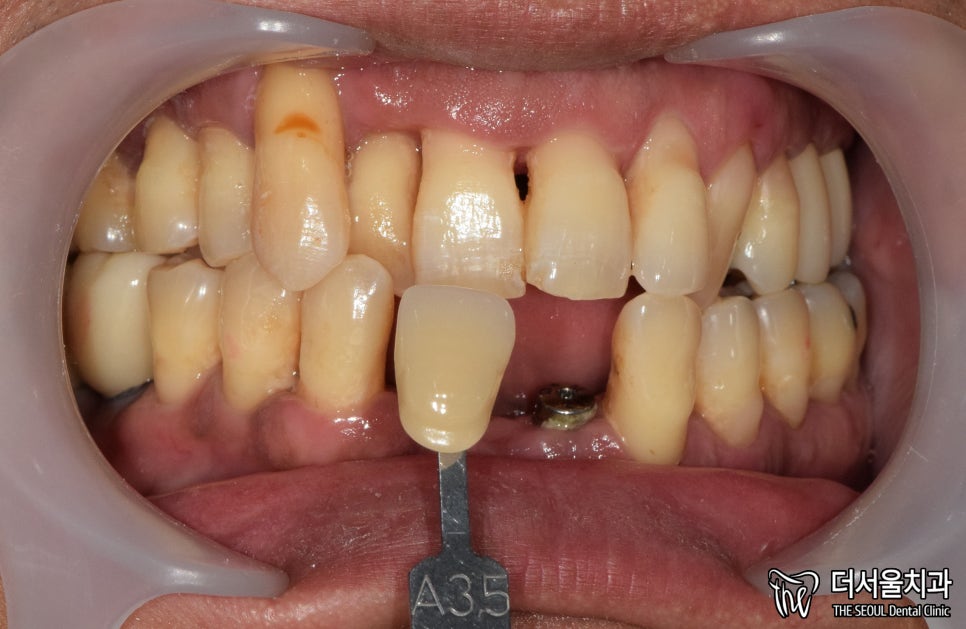

먼저 사진을 보겠습니다.

여러분이 보더라도

구강 상태가 심각하다는 걸 알 수 있습니다.

올바른 교합이 이뤄질 수 없을 뿐더러

치경부 마모증에 쌓여있는 치석에 충치까지

손댈 부분이 너무 많네요.

게다가 구취까지 나고 있었기에

걱정되는 상황이었습니다.

그 사이에 최종 보철은 어떤 색으로 만들면 좋을지

쉐이드 가이드를 이용하여

남아있는 치아의 색과 비교합니다.

A3.5가 비슷해서 해당 색으로

보철 제작에 들어갔습니다.